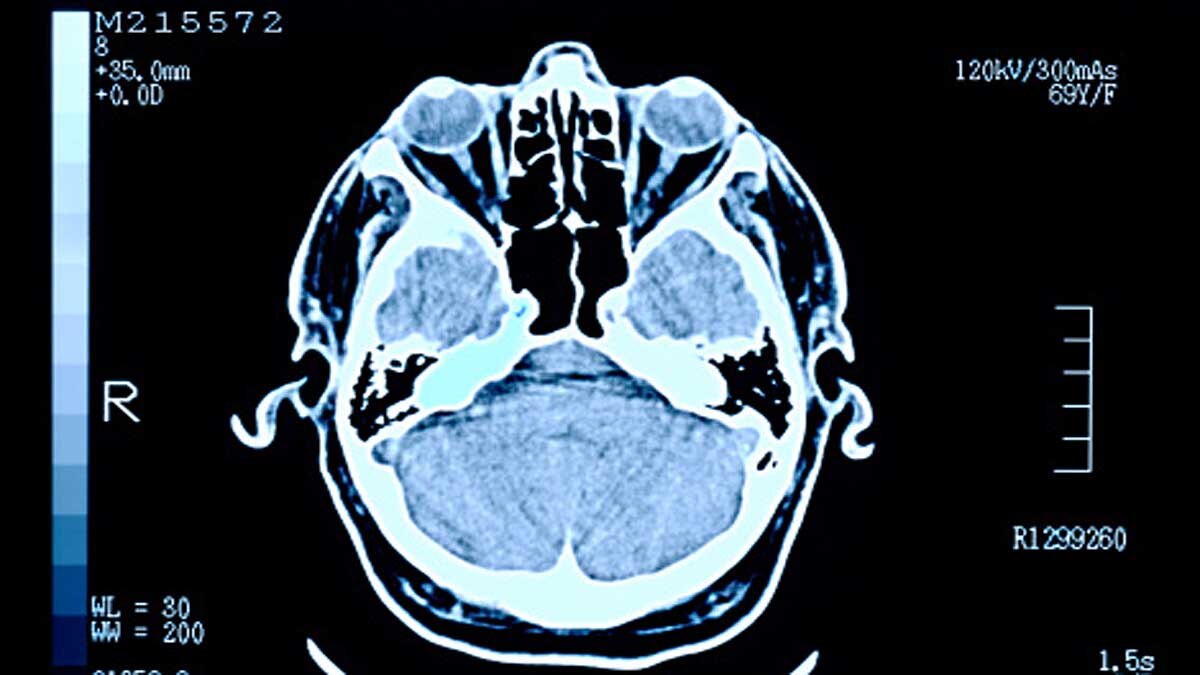

इंसानों के पूर्वज थे वानर...लेकिन इंसानों के दिमाग वानरों से बड़ा क्यों हैं? इस बात का पता वैज्ञानिकों ने लगा लिया है. अपने सबसे नजदीकी प्राइमेट संबंधी की तुलना में इंसानों का दिमाग का आकार काफी बड़ा है. इस बात का खुलासा करने के लिए साइंटिस्ट्स ने इंसानों, चिम्पैंजी और गोरिल्ला के दिमाग से कोशिकाएं लीं. उसके बाद उन्हें प्रयोगशाला में विकसित कराया. तब जाकर पता चला कि इंसानों के शरीर में एक ऐसा स्विच होता है जिसके दबने से इंसानों का दिमाग ही नहीं कई अन्य अंग वानरों की तुलना में तीन गुना बड़े हो जाते हैं. (फोटोःगेटी)

एक सामान्य स्वस्थ इंसान के वयस्क होने पर दिमाग का आकार 1500 घन सेंटीमीटर का हो जाता है. जबकि, गोरिल्ला का दिमाग 500 घन सेंटीमीटर और चिम्पैंजी का दिमाग 400 घन सेंटीमीटर होता है. वैज्ञानिकों के सामने अब भी यह दिक्कत है कि इंसानों और वानरों के विकसित होते दिमाग के रहस्यों को सुलझाया जा सके. किसी भी जीव का दिमाग खासतौर से इंसानों का आज भी एक पहेली है. (फोटोःगेटी)